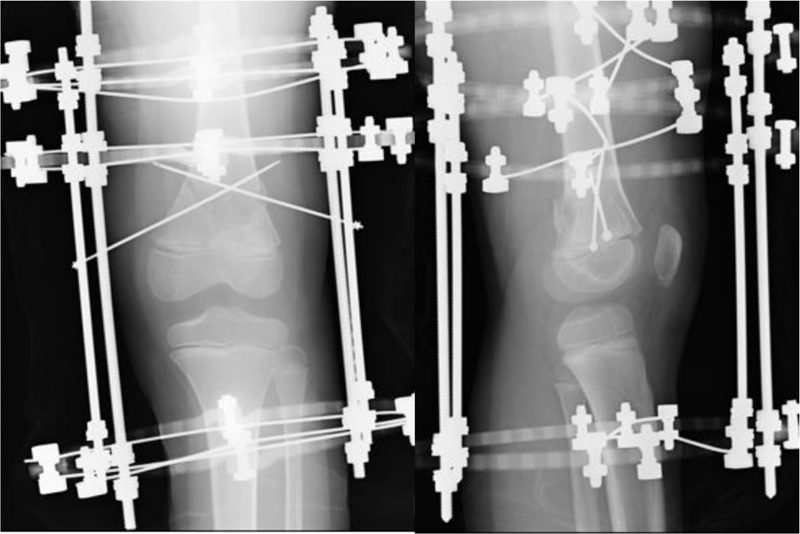

Our case was a 9-year-old boy who had a skiing accident. He complained of severe pain in his left knee and swelling. After evaluating the radiograph, we diagnosed a Salter-Harris type-II fracture of the distal femoral epiphysis (Fig. 1). The Computer Tomography scan showed displacement of the epiphysis into the valgus, angulation, and flexion. Under general anesthesia, we performed percutaneous pin fixation with circular external fixation. First, we inserted two straight wires into each distal femur and proximal tibia. We attached full rings and performed closed reduction with distraction. After closed reduction, we inserted 2 Kirschner wires crossing from medial and lateral distal femoral metaphyses without crossing the physis. Permanent fixation was performed using 2 full rings for distal femur and a full ring for proximal tibia (Fig. 2). Immediately after surgery, he was allowed to walk with full weight bearing. Six weeks after surgery, we removed the external fixation under the nerve block, confirmed radiographic bone union, and started a knee range-of-motion exercise in addition to full weight bearing.